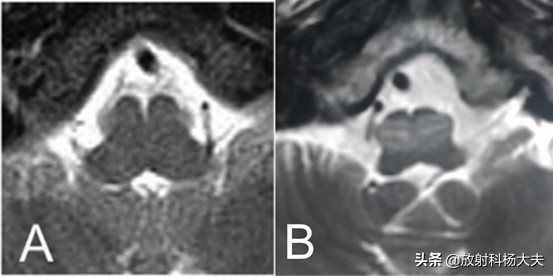

比如今天,我们的一线大夫在一个患者的头颅核磁里偶遇一只“忍者神龟”。

左边是患者的头颅核磁,右边就是伴随我整个童年的英雄--忍者神龟!

图A是正常人的延髓,图B是患者下橄榄核层面的延髓

从图片上,我们可以看出患者下橄榄核T2WI信号明显增高,并且体积增大,表现出明显的占位效应,还有一个特点就是非常对称。一线大夫考虑到病变有明显的占位效应,又结合各个序列的信号特点,考虑了肿瘤、炎性病变、脱髓鞘类疾病等,但是觉得这个形态和信号上的完全对称十分奇怪,举棋不定下写下了“建议结合临床进一步核磁增强检查”。

上级签片医生注意到患者桥脑有陈旧性出血改变,累及双侧中脑被盖,如下图。

如果把两个病灶一起考虑的话答案就清晰了,其实这是一个“肥大性下橄榄核变性(Hypertrophic olivary degeneration,HOD)“的表现,无需进一步增强检查,避免了因过度检查给患者造成经济负担。